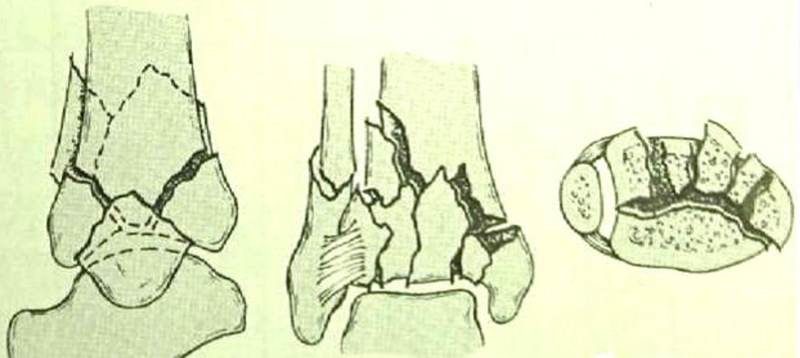

临床常以Ruedi-Allgower分型作为损伤分型。

图5 Ⅲ型:严重的关节面粉碎和干骺端嵌压的移位骨折